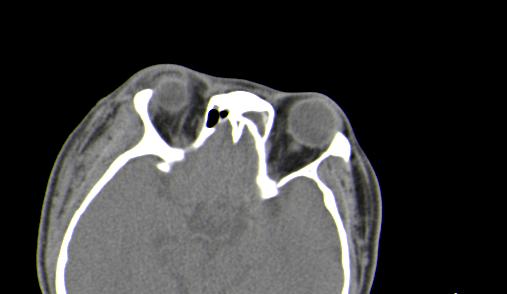

以下是引用皎皎白驹在2006-11-29 8:48:00的发言:[br]影像表现:双侧筛窦和上颌窦、鼻腔内均密度增高,右侧视神经增粗、弯曲,左筛窦顶部筛板及右侧纸板近视神经孔区可见骨折线。[br]结合临床表现考虑:右侧筛窦纸板近视神经孔区骨折致右侧视神经损伤。最好做个眼眶冠状扫描,更明确右侧视神经管是否狭窄。

以下是引用w_jianhua在2006-11-29 10:07:00的发言:[br]影像表现:双侧筛窦和上颌窦、鼻腔内均密度增高,右侧视神经增粗、弯曲,左筛窦顶部筛板及右侧纸板近视神经孔区可见骨折线。[br]结合临床表现考虑:右侧筛窦纸板近视神经孔区骨折致右侧视神经损伤。最好做个眼眶冠状扫描,更明确右侧视神经管是否狭窄。 [br] [br]支持[br]

以下是引用守望可可西里在2006-11-29 9:46:00的发言:[br][quote]以下是引用皎皎白驹在2006-11-29 8:48:00的发言:[br]影像表现:双侧筛窦和上颌窦、鼻腔内均密度增高,右侧视神经增粗、弯曲,左筛窦顶部筛板及右侧纸板近视神经孔区可见骨折线。[br]结合临床表现考虑:右侧筛窦纸板近视神经孔区骨折致右侧视神经损伤。最好做个眼眶冠状扫描,更明确右侧视神经管是否狭窄。